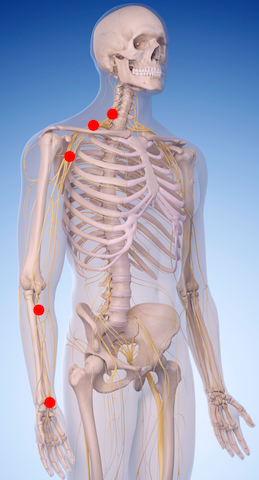

Numbness and tingling in the arms and hands is a common complaint I hear from my patients. The two most common causes I have observed is either a pinched nerve (in the neck, shoulder, chest, forearm, and/or wrist) or a muscle knot in a shoulder or forearm muscle.

The nerves in your arm and hand come from you brain and travel down your spinal cord. The nerves then exit your spine in your neck and weave in and out of muscles to make their way down to your finger tips. Any misaligned bone (spinal, shoulder or elbow bone) or muscle can compress or pinch your nerve and cause numbness and tingling. Once you find out where the nerve is being pinched you can get the proper treatment to take the pressure off the nerve.

Muscles that get overused tighten up and get knots. These muscle knots (trigger points) can cause numbness or tingling in your hands as well. This is very common as many people are sitting all day at a desk typing and mousing. First, the constant typing and mousing lead to muscle knots and strain injuries in the forearm and wrist. Second, the prolonged sitting leads to muscle knots and postural strain of the back and neck muscles.

Numbness/tingling is likely coming from the muscle knots in your neck, shoulder, chest, or forearm muscles if: